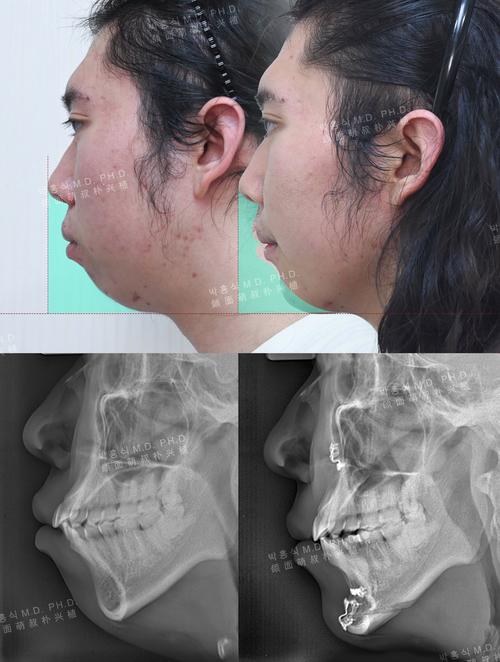

- 曲面断层片:观察牙根位置、牙槽骨高度及恒牙发育情况,排除牙源性因素。

- 头颅侧位片:分析颌骨位置关系(如下颌平面倾斜度、上下颌突度)、软组织轮廓,评估骨性不对称程度。

- CBCT:三维重建颌骨及牙齿结构,精确测量中线偏移量、牙根倾斜度及牙槽骨对称性,为治疗方案设计提供依据。